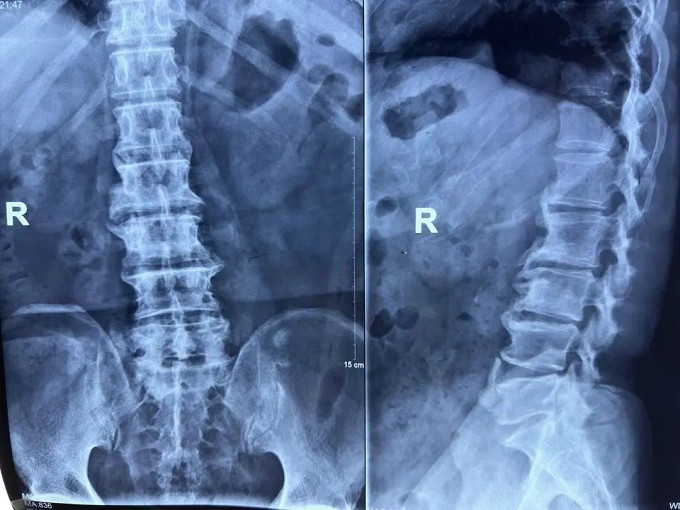

術(shù)前

X線片